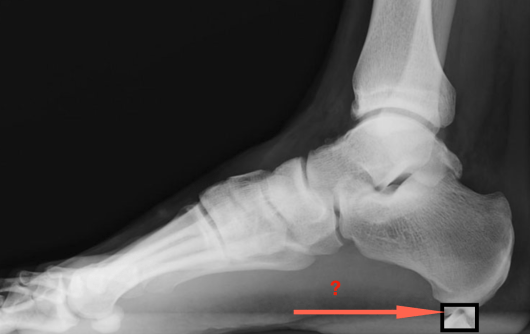

De quoi s’agit-il ? Comment l’imaginez-vous (si on ne vous l’a pas montrée) ? Cela « devrait » faire mal si cela ressemble à ceci (image ci-dessous)

Anatomiquement, s’agit-il de ceci ? (qui devrait faire mal)

Ou de ceci ? (qui devrait faire mal)

Eh bien non, il s’agit de ceci ! Et qui ne « pique » pas…

Qu’en est-il de cette fameuse épine qui ne pique pas ? L’épine de Lenoir est une trouvaille radiologique. Elle se situe à l’origine de l’insertion des courts fléchisseurs des orteils. Elle est observable chez 50 % des cas de fasciite plantaire et chez 15 % de la population asymptomatique. Elle n’entraîne pas de douleur en soi et il n’y a pas de lien précis entre l’épine et la fasciite (aponévrosite plantaire).